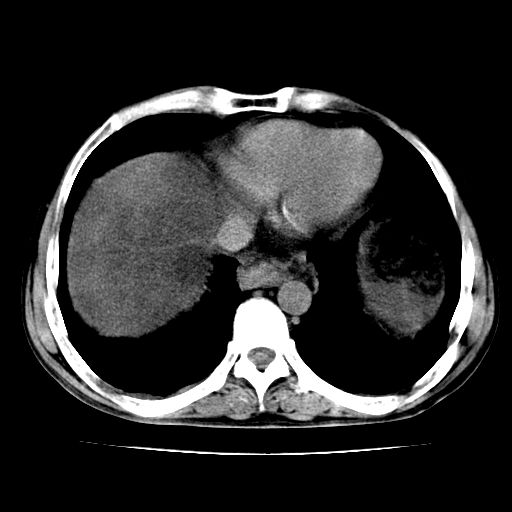

男,55岁,发现“肝硬化”5年,现腰疼、腹胀10余日,巩膜黄染、腹稍胀,肝肋下3指,质硬无压疼,移动性+,血生化:总胆、直胆、间胆均升高。

g1:肝硬化、脾大、腹水。

2:脂肪肝。

3:弥漫性肝癌待排。

肝硬化,脾大,腹水

脂肪肝

肝内多发低密度灶(建议增强扫描除外肝癌)

肝脾肿大,脂肪肝,腹水。建议增强除外肝癌。